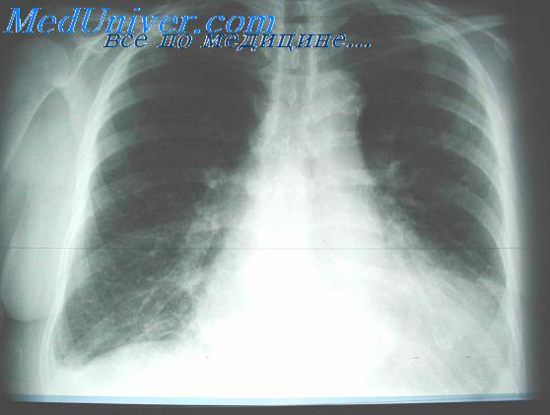

Затяжное течение отека легких (от 12 часов до нескольких суток) наблюдается при хронической почечной недостаточности, системном васкулите, склеродермии, хронических воспалительных заболеваниях легких. Нередко протекает без одышки, цианоза, пенистой мокроты и влажных хрипов в легких (клинически как стертая форма или интерстициальный отек легких). Течение отека легких не всегда определяется нозологической формой основного заболевания. Так, при инфаркте миокарда встречаются не только острая и подострая формы отека легких, но и затяжное течение. Интерстициальный отек легких, например, при инфаркте миокарда может протекать бессимптомно и обнаруживается лишь при рентгенологическом исследовании. Рентгенологическое исследование помогает утвердить клиническое предположение отека легких. При прямой и боковой проекциях в период интерстициального отека легких находят так называемые линии Керли (тонкие линии, сопровождающие висцеральную и междолевую плевру в базально-латеральных и прикорневых отделах легочных путей), отражающие отечность междольковых перегородок, усиление легочного рисунка в связи с инфильтрацией периваскулярной и перибронхиальной межуточной ткани, особенно в прикорневых зонах. При этом корни легких теряют свою структуру, очертания их становятся размытыми. На всем протяжении легочных полей отмечается понижение их прозрачности, определяется нечеткость легочного рисунка: в периферических отделах видна отечность.